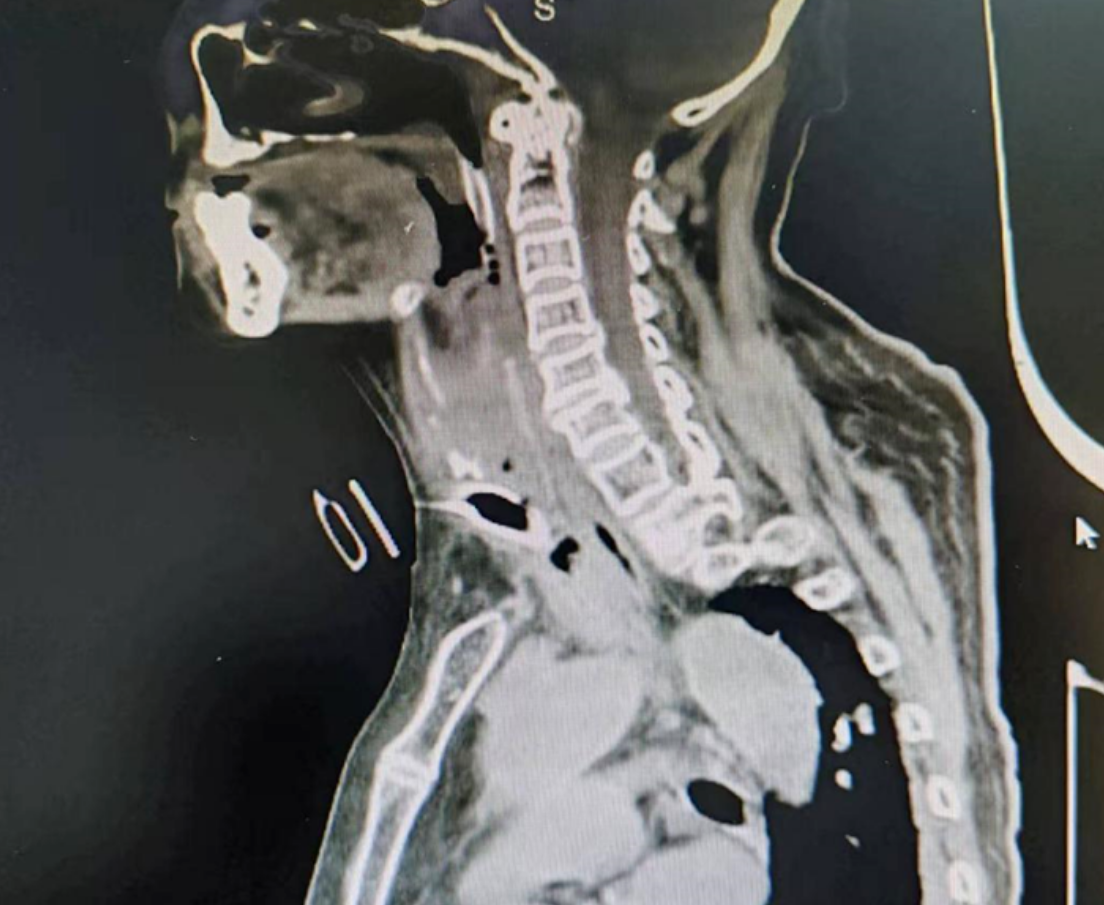

周阿姨带着气管套管已有一段时间,去了多家医院均未能成功拔除。入院后,粤东医院康复医学科立即组织医生研究患者既往病历,床边评估后发现,周阿姨试堵管时存在明显的呼吸困难,颈部听诊提示上气道通畅性差,详细查看影像学,CT提示上气道及声门下部存在异常。

李先主任团队立即对患者进行纤维支气管镜检查,问题出现了:1、声门上黏膜肿胀、声门狭小;2、声门下气切口附近约1cm肉芽肿物伴水肿,导致气道严重狭窄。李先主任立即组织团队讨论,结合患者目前情况,如果贸然行介入消融手术治疗,操作风险高,术中出血几率较高,决定先予激素治疗(于8月19日开始局部注入地塞米松+布地奈德口鼻雾化+甲泼尼龙40mg静滴)+无创辅助通气维持上气道功能。

8月29日,李先主任带领团队在支气管镜室静脉麻醉+局麻下行介入消融治疗。镜下见气管上段肉芽增生致气管狭窄,几乎完全堵塞。经过2个小时的努力,团队成功完成介入手术,术后气管通畅。